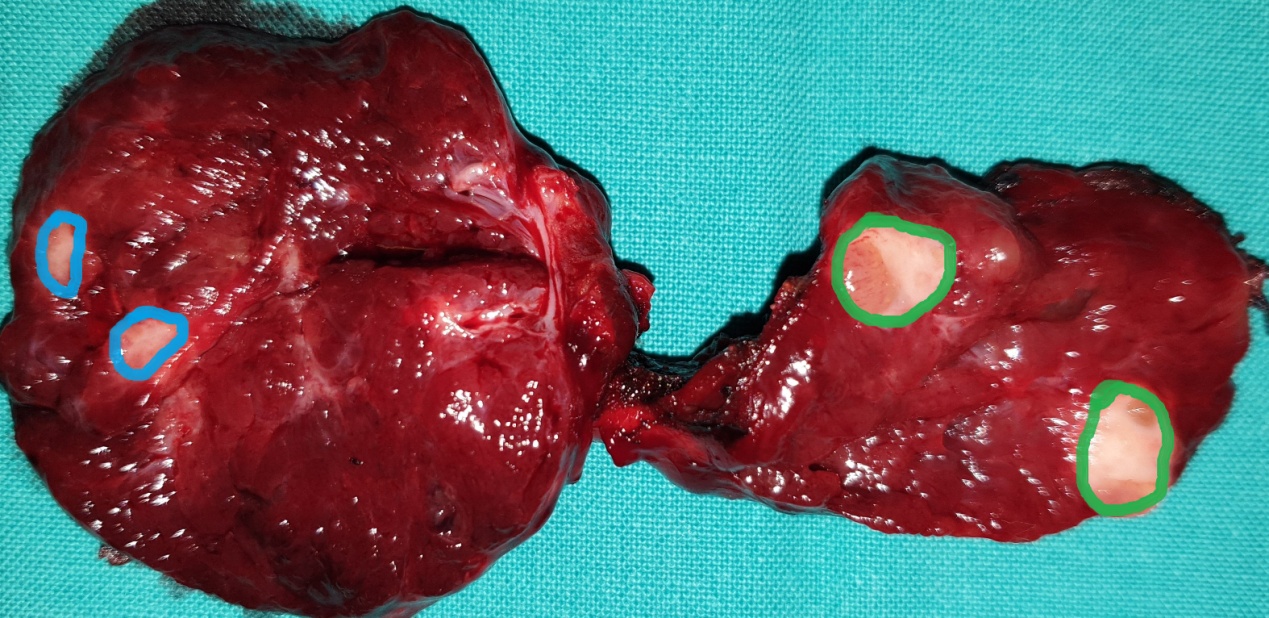

Figure 5 . Surgical specimen a) Blue arrows: encapsulated medullary microcarcinoma b) Yellow arrows : parathyroid glands . c) Green arrow : Benign thyroid nodule . ( Courtesy Dr . V . Penopoulos ) .

Green outline: Papillary carcinoma of the right thyroid lobe. Blue outline: Medullary carcinoma of the left thyroid lobe (Courtesy Dr. V. Penopoulos)

Type III. Green arrows: Sectioned papillary carcinoma of the right thyroid lobe. Blue arrow: Medullary carcinoma of the right thyroid lobe. The two cancers are clearly separated by normal thyroid parenchyma (Courtesy Dr. V. Penopoulos)